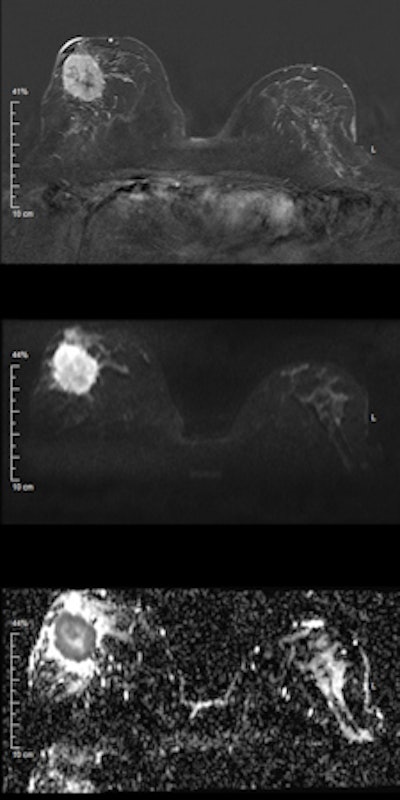

Invasive ductal carcinoma. Top: Early contrast-enhanced T1-weighted subtraction image depicting a large mass lesion in the right breast. Middle: Diffusion-weighted image at b = 1000 s/mm2 shows high signal corresponding to the contrast enhancement in the first image. However, in this case, the signal is due to restricted diffusion, meaning that no external contrast agent was used. Bottom: Quantitative parametric diffusivity map of apparent diffusion coefficient (ADC) values. Dark pixels correspond to restricted diffusion, while bright pixels correspond to increased diffusion. In the outer part of the tumor, dense clusters of cancer cells cause restricted diffusion; the diffusion measured by DWI is mainly caused by extracellular diffusion. Clearly, diffusivity is elevated inside the center of the lesion, corresponding to necrosis, which is indicative of a very aggressive cancer. All images courtesy of Dr. Pascal Baltzer.